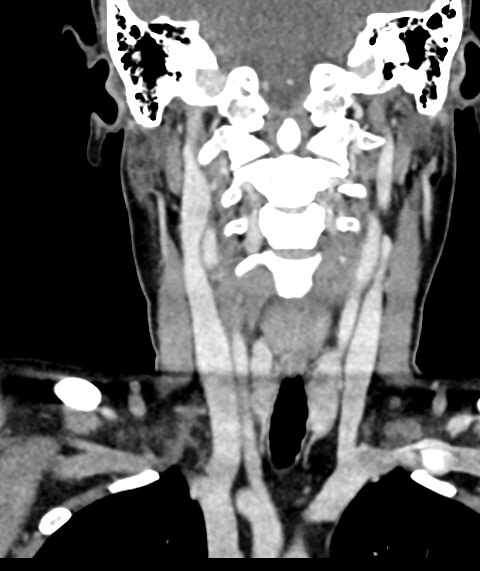

Мультиспиральная компьютерная томография – это высокоинформативный лучевой метод диагностики различной патологии мягких тканей шеи, включая воспалительные заболевания, травматические повреждения и опухолевые процессы. КТ позволяет оценить состояние щитовидной железы, паращитовидных желез, гортани, верхней части пищевода, магистральных сосудов шеи, шейных лимфоузлов и окружающих мягких тканей.

Метод КТ основан на применении рентгеновского излучения. Однако в отличие от обычного рентгена, при котором снимки производятся в одной плоскости, при КТ излучатель рентгеновских лучей постоянно двигается вокруг объекта исследования, проводя сканирование в различных плоскостях, а затем трансформируя полученные данные в цифровые трехмерные изображения. Это дает возможность визуализировать органы и ткани в мельчайших подробностях, а с помощью объемных 3D-реконструкций наглядно оценить пространственное расположение органов и патологических образований.

Рентгеновские лучи лучше всего поглощаются плотными структурами, такими как костная ткань. Поэтому кости хорошо видны на снимках КТ. Это делает компьютерную томографию незаменимой при необходимости обследования, в частности, костного скелета гортани. Однако для улучшения визуализации мягких тканей требуется введение специального контрастного препарата, поэтому КТ мягких тканей шеи проводится с контрастным усилением.

Для контрастирования используется йодсодержащее контрастное вещество, которое в составе рентгеноконтрастного препарата вводится в вену пациенту непосредственно во время исследования. Благодаря способности контраста поглощать рентгеновские лучи на снимках КТ хорошо контрастируются кровеносные сосуды и опухолевые образования, имеющие, как правило, развитую сосудистую сеть. Методика внутривенного болюсного контрастирования помогает обнаружить воспалительные изменения, отличить доброкачественные опухоли от злокачественных, выявить поражение лимфатических узлов и степень прорастания опухоли в магистральные сосуды и окружающие ткани.